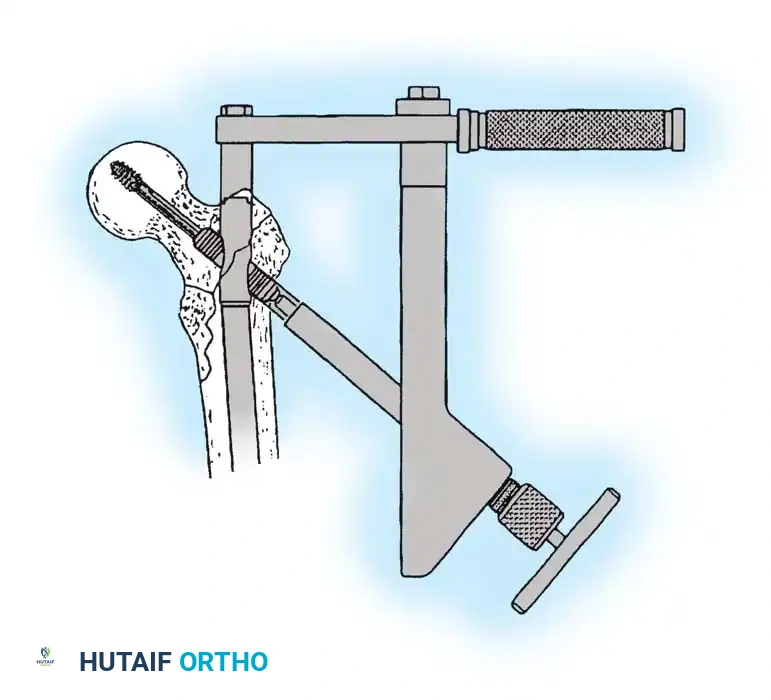

4. Reaming and Lag Screw Insertion

Once the guide wire is perfectly positioned, the lateral cortex is opened, and the femoral neck is reamed over the wire.

Reaming of the femoral neck and head over the precisely placed guide wire, preparing the channel for the lag screw.

The lag screw is then inserted. It is crucial not to over-insert the screw, which can penetrate the articular cartilage, nor to under-insert it, which compromises fixation.